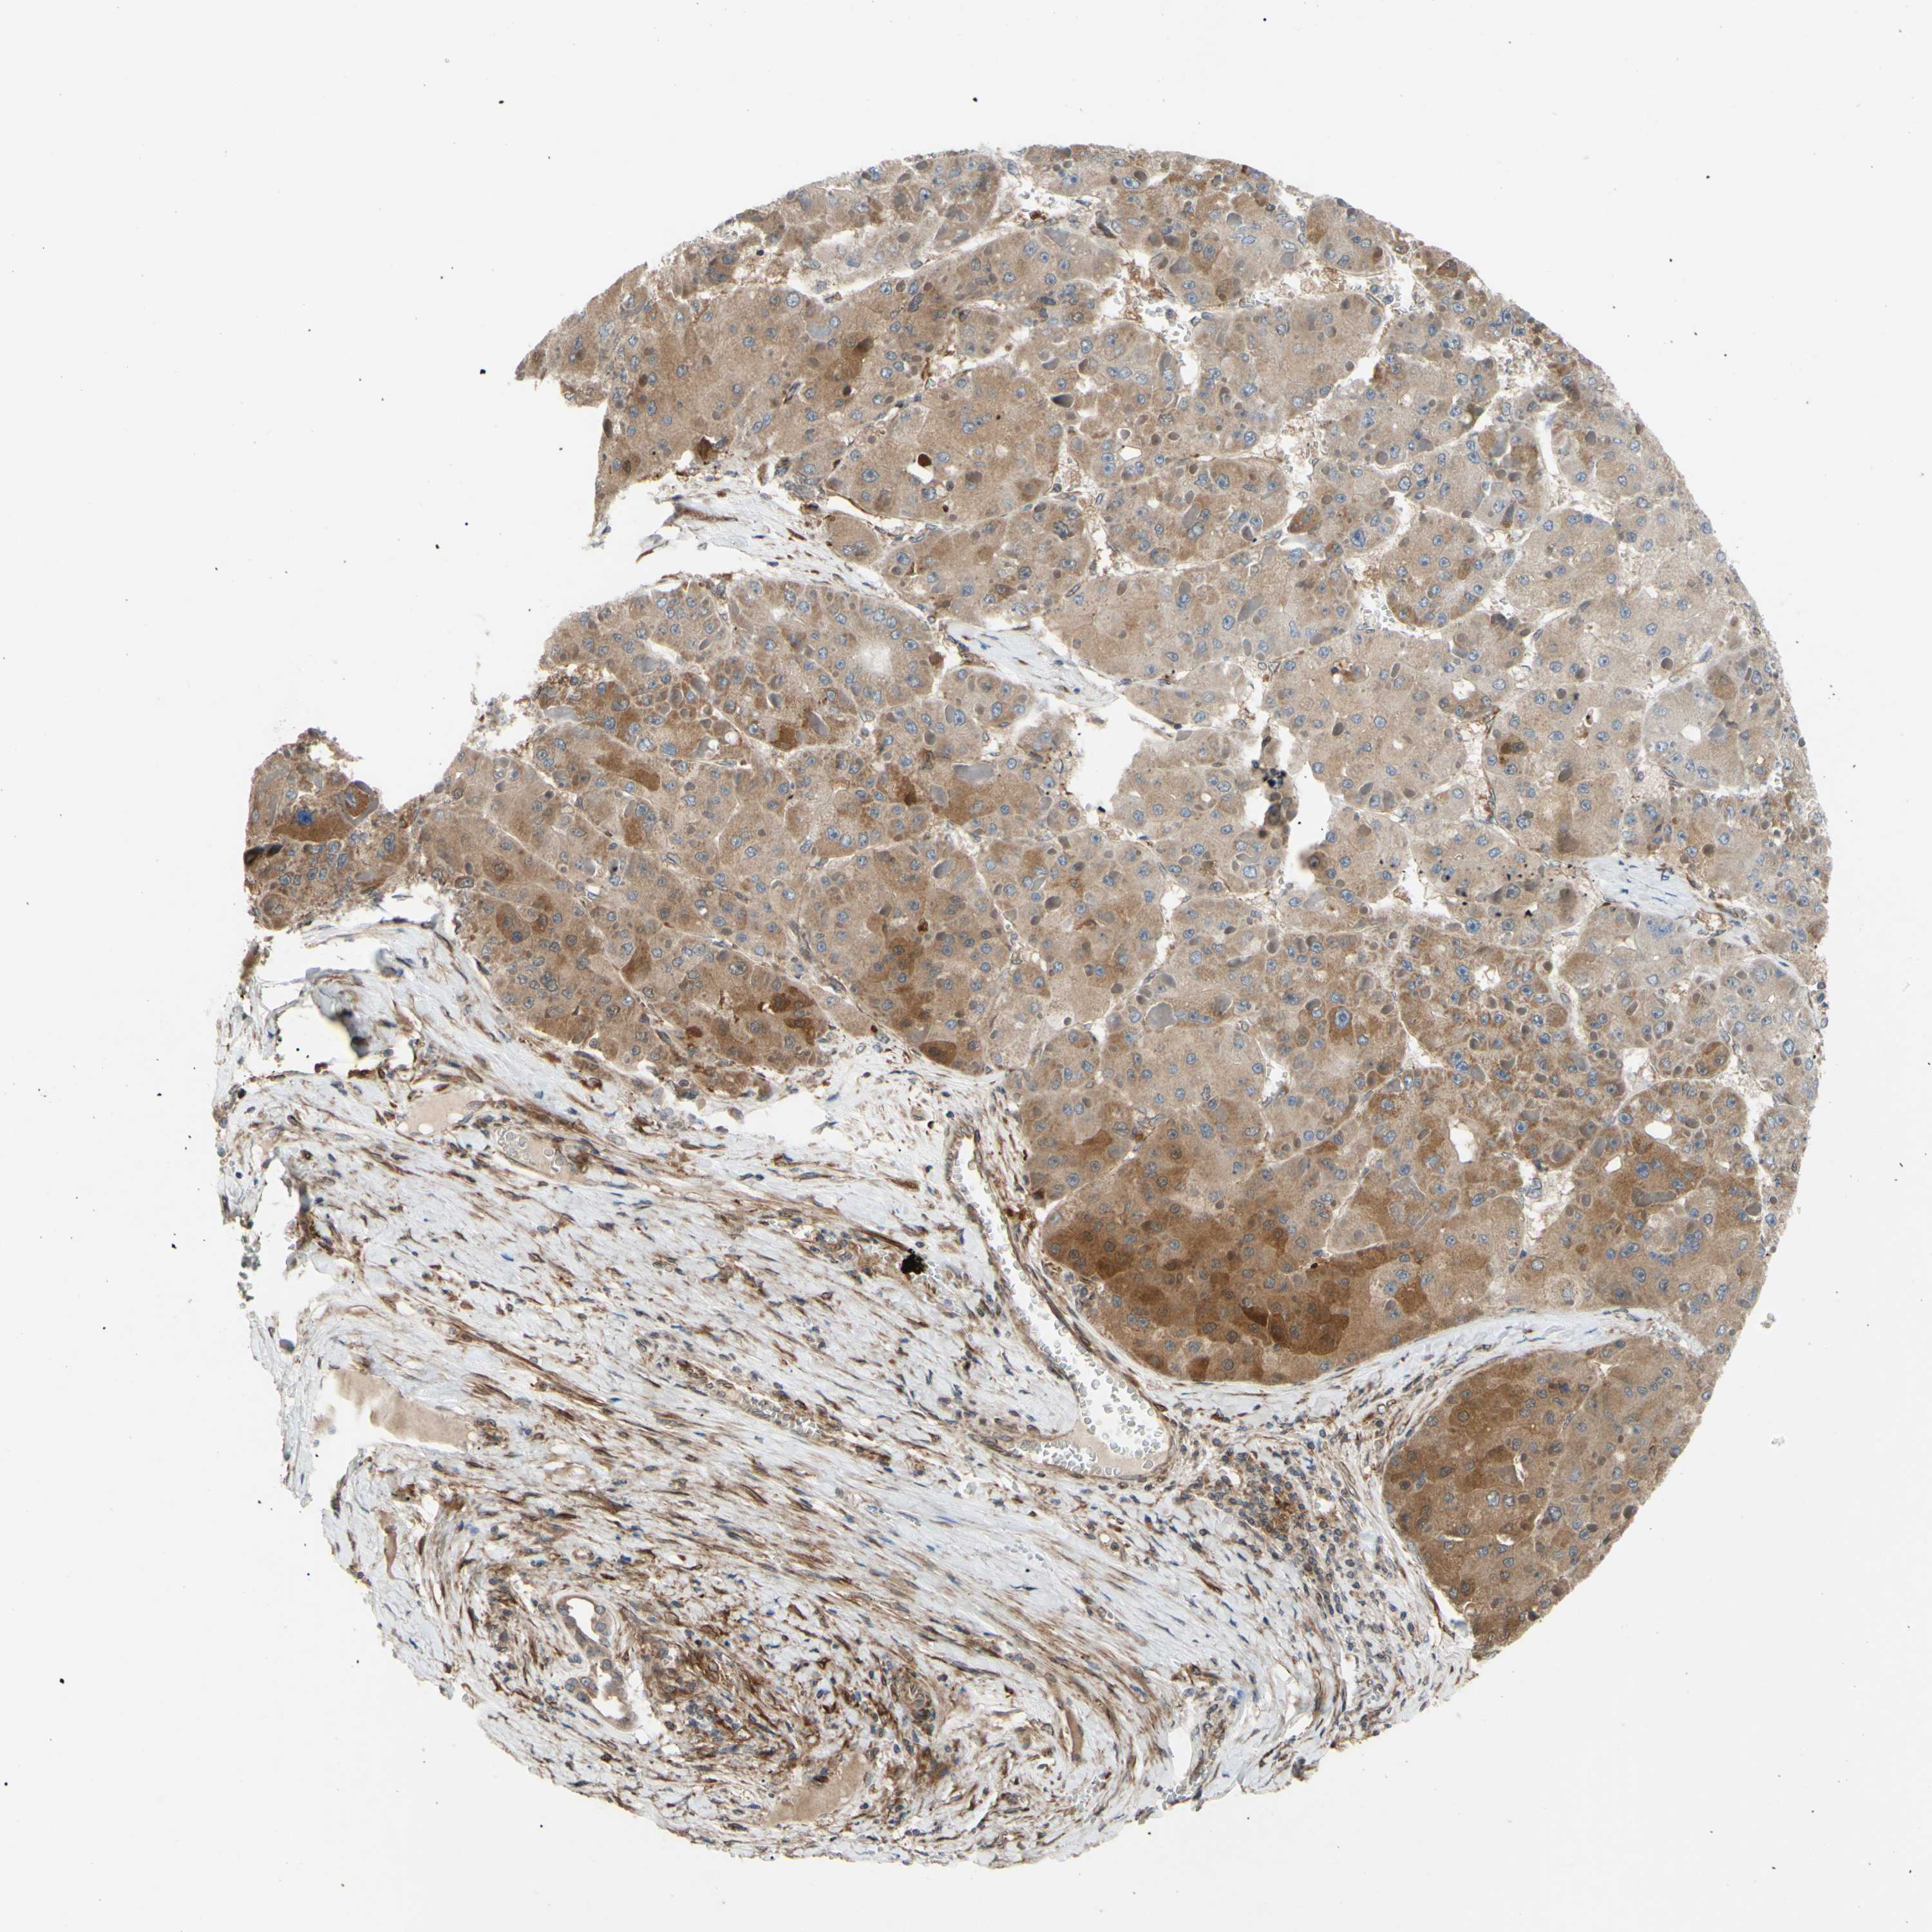

LIVER CANCER - Protein expressioni

A mouse-over function shows sample information and annotation data. Click on an image to view it in a full screen mode. Samples can be filtered based on level of antibody staining by selecting one or several of the following categories: high, medium, low and not detected. The assay and annotation is described here.

Note that samples used for immunohistochemistry by the Human Protein Atlas do not correspond to samples in the TCGA dataset.

Antibody stainingi

Antibody staining in the annotated cell types in the current human tissue is reported as not detected, low, medium, or high, based on conventional immunohistochemistry profiling in selected tissues. This score is based on the combination of the staining intensity and fraction of stained cells.

Each image is clickable and will lead to virtual microscopy that enables deeper exploration of all samples and also displays staining intensity scores, fraction scores and subcellular localization as well as patient and tissue information for each sample.

Antibody HPA002859

Antibody CAB011655

Staining

High

Medium

Low

Not detected

Intensity

Strong

Moderate

Weak

Negative

Quantity

>75%

75%-25%

<25%

None

Location

Nuclear

Cytoplasmic/membranous

Cytoplasmic/membranous,nuclear

Carcinoma, Hepatocellular, NOS

Cholangiocarcinoma